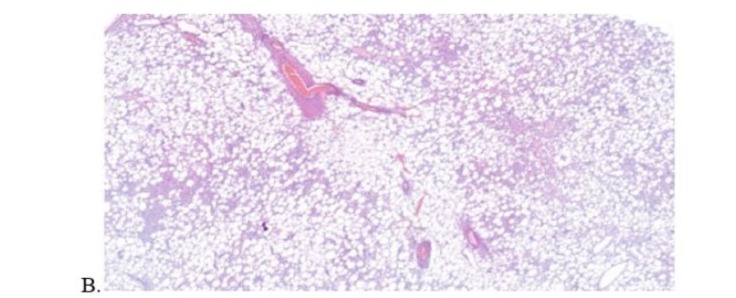

In all cases, both the immediate and late postoperative periods were uneventful. Microscopic and immunohistochemical analysis of the pathological anatomy confirmed the presence of AML (figure 7). Serial sections showed a proliferation of adipose tissue, smooth muscle and blood vessels. The tissued stained positive for actin and negative for cytokeratin.

Figure 7: Main pathological anatomy findings. (A. Macroscopic study, B. Microscopic study, C. Immunohistochemical studies -actin and cytokeratin-)